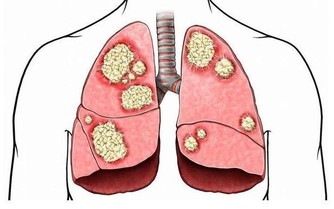

多汗的第一判斷1.夜間盜汗→ 結核病結核病典型的全身表現中包括午後低熱和夜間盜汗。

很多患者都反映無論春夏秋冬,晚上睡覺醒來後常常衣服被子全部都被汗水浸濕。

結核病在中國是一個比較令人頭疼的健康問題,所以你親愛的他如有上述症狀你就需要和醫生交流了。